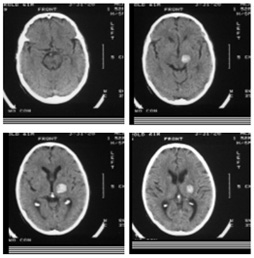

• 3D递归脑出血量化

• 计算断层摄影允许三维解剖成像脑异常,如人自发后脑出血使用计算机图像分析,对选定兴趣量的病理学定性是可行的拟议的研究侧重于三维量化分析研究ICH早期演化基础假设ICH量和结构与死亡率和发病率相关拥有ICH的病人四次扫描:3小时后发症,1小时后发症,8小时后发症,20小时后发候发症疾病过程期间,可观察分析ICH体积和结构三维变化重要ICH特征为体积、空间定位和主水深和水深区域形状初步研究表明ICH体积对病人生存意义重大空间位置必须用不变三维坐标系测量,这样ICH横跨扫描运动才能确定实现不变性需要从两次扫描中执行脑CT图像注册最近开发出迭代主Axes注册算法 注册三维多模式脑图像并开发三维空间加权区域增长算法 并适应聚类分割ICH区域最后,形状特征将计算成ICH进化与死亡率和发病率相关联此外,ICH特征行为可与病人对医疗响应相关联,目的是评价疾病过程早期的治疗期望拟议的研究能提供计算机化系统分析ICH,通过ICH体积和结构在疾病过程的特征变化分析ICH